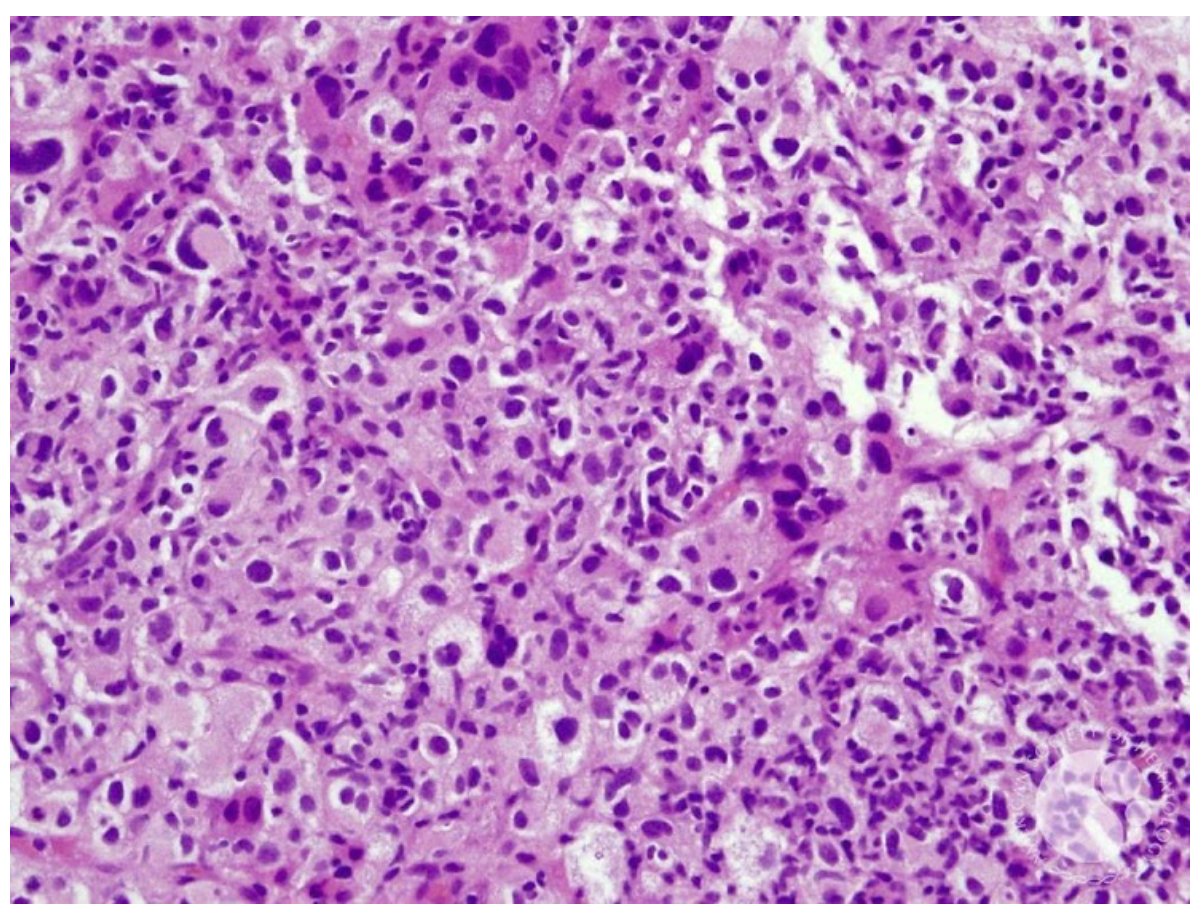

Homem, 52 anos, portador de linfoma folicular grau 1, em seguimento clínico há 4 anos, sem necessidade de tratamento até o momento. Procura atendimento devido surgimento de nódulo de crescimento rápido em parede torácica, febre e perda ponderal. Biópsia da lesão mostrada abaixo. Imunohistoquímica: CD45 positivo, CD19 negativo, CD20 negativo, CD10 negativo, CD3 negativo, CD7 negativo, CD2 negativo, CD5 negativo, CD4 positivo, CD8 negativo, MPO negativo, CD13 negativo, CD33 negativo, CD34 negativo, TdT negativo, HLA-DR positivo, CD163 positivo, CD68 positivo, lisozima positiva, CD1a negativo, CD21 negativo e Ki67 80%. Neste caso, qual a principal hipótese diagnóstica?

B) SACROMA HISTIOCÍTICO

O sarcoma histiocítico é uma neoplasia derivada de células histiocitárias teciduais maduras.

Ocorre geralmente em adultos e pode estar associado a neoplasias linfoides, principalmente linfoma folicular e leucemia linfoide crônica, correspondendo a fenômeno de transdiferenciação.

No anatomopatológico, observa-se infiltrado difuso constituído por grandes células, podendo ser indistinguível do linfoma difuso de grandes células B.

Tem localização EXTRANODAL, mais comum no trato gastrointestinal, pele e partes moles, podendo se manifestar como lesão única ou múltiplas lesões.

Sintomas constitucionais são frequentes e pode haver hepatoesplenomegalia.

O infiltrado é constituído por grandes células, algumas fusiformes, e tem aspecto bastante POLIMÓRFICO.

O citoplasma é eosinofílico, o núcleo excêntrico e a presença de células multinucleadas é comum.

Pode haver infiltrado inflamatório proeminente, podendo inclusive ocultar as células neoplásicas.

Na imunohistoquímica, deve haver expressão de um ou mais marcadores histiocíticos: CD163, CD68 e lisozima.

Devem estar ausentes marcadores de células de Langerhans (CD1a e langerina), células dendríticas foliculares (CD21 e CD35) e células mieloides (MPO e CD13).

Pode haver expressão fraca de CD15.

CD45, CD45RO e HLA-DR também são POSITIVOS.

S100 costuma ser positivo fraco e focal.

CD4 é frequentemente positivo.